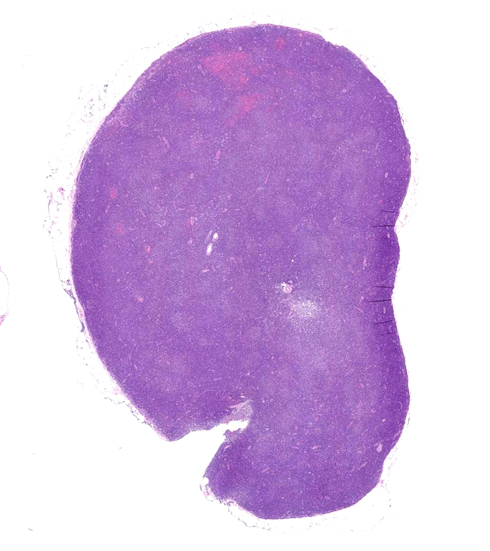

Chronic lymphocytic leukaemia/small lymphocytic lymphoma†

頸部リンパ節では, 正常構造は消失し, びまん性小型リンパ球の密な増殖ありproliferation center様構造が散在する。CD20,CD19,CD5,CD23,CD25陽性。cyclinD1陰性。lambda light chain 陽性細胞98%, 核間期細胞FISHで13q14.3単一シグナルが38%の細胞に検出(monosomy 13)された.

組織像・組織所見†

- リンパ節正常構造は小型成熟リンパ球の単調でdensなびまん性増殖によりぼぼ全体にわたり消失する。

pseudofollicleまたはproliferation center

- CLL/SLLの組織学的Hallmarkで,90%以上の症例に出現するとされる

- 弱拡大では, 暗調で均一な背景の中に境界の不明瞭な, または癒合する, やや明るい類円形の領域が視認できる.

この部位ではやや広めの細胞質と明瞭な中心性核小体を特徴とするparaimmunoblastと, 同様の形態でわずかに小型のprolymphocyteと呼ばれる腫瘍細胞が集蔟する場所である。

- 背景の暗調領域を構成する細胞は小型で非腫瘍性小型リンパ球との区別が困難であるが, 正常リンパ球より一回り大きめのことが多く, 核クロマチンのclumpingのため核内構造が見えやすい印象がある。小さな核小体を持つ場合もある。